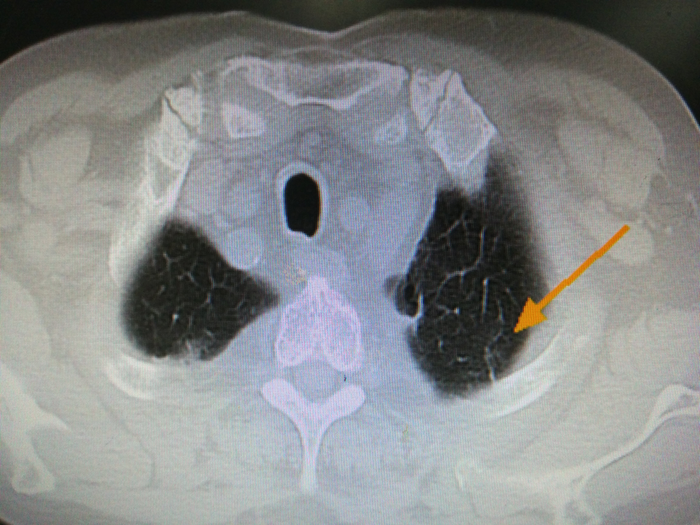

左上肺条索影

活检加单针射频消融,一共30min,非常顺利,没有气胸,没有咯血。做完第二天,周老师就出院了。病理提示前列腺癌肺转移可能。6个月后,他第二次来复查。CT上磨玻璃影已经消失了,只剩下一个条索影。周老师很激动,不住的夸他自己慧眼识英雄,在众多治疗中选对了射频,选对了医生?